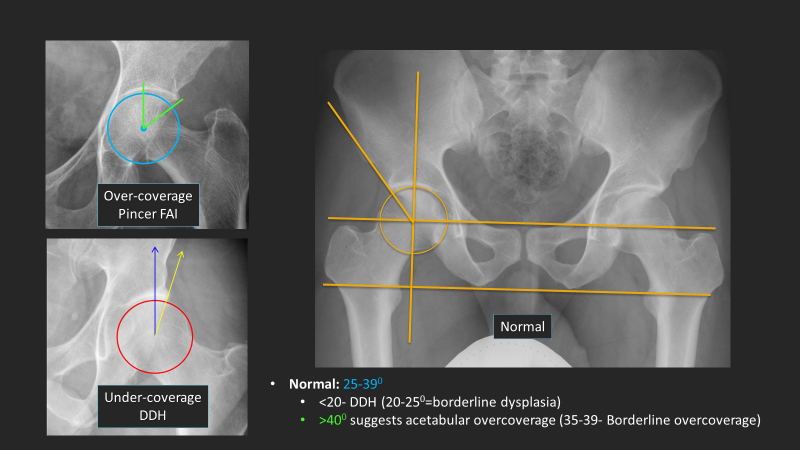

A beautiful Stener lesion passing through your timeline to make your day better! Society of Skeletal Radiology SSR_RWG RSNA International Skeletal Society | ISS ACRadiologia Skeletal Radiology European Society of Musculoskeletal Radiology